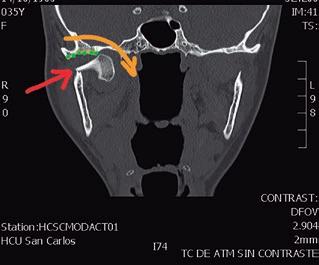

SFIG. 1, a-e. Fractura subcondílea derecha tipo V de Spiessl en una paciente joven tras un accidente doméstico. a) OPG preoperatoria donde se aprecia la línea de fractura subcondilar derecha con desplazamiento fragmentario (flecha roja) y el movimiento de dislocación ántero-medial que ha realizado el fragmento condilar (flecha amarilla); la paciente había sufrido una fractura orbitaria hacía unos años, observándose una miniplaca de titanio colocada en el reborde infraorbitario izquierdo. b) Corte axial y densidad hueso de la TC con el fragmento condilar dislocado adelante hacia medial muy cercano a la apófisis pterigoides (flecha verde) aunque con aparente contacto entre fragmentos (flecha roja). c) Corte coronal de la TC con el desplazamiento entre fragmentos (flecha roja) y la dislocación hacia medial (flecha amarilla) fuera de la fosa glenoidea (puntos verdes). d) Vista anterior de la reconstrucción 3D con sustracción de estructuras de la TC en la misma fractura. e) Vista póstero-lateral de la misma reconstrucción; estas imágenes son muy útiles durante la cirugía para apreciar los movimientos en los tres planos del espacio que realizó el fragmento condilar, aunque solamente informa de las estructuras óseas y no de los tejidos blandos.